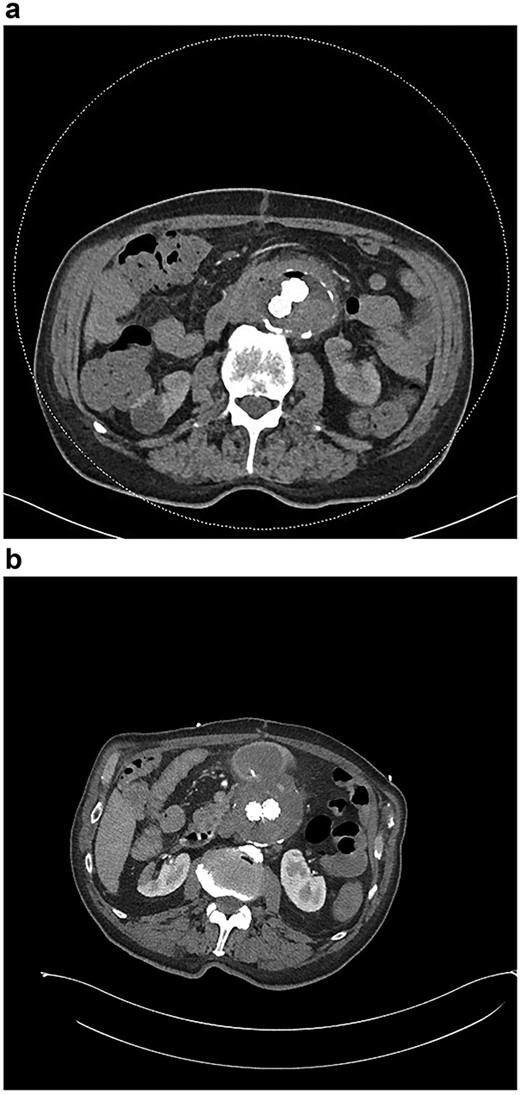

A stent with iliac limb extensions was deployed. EndoAnchors (Medtronic) were applied proximally. Final angiogram demonstrated patent renal and iliac arteries but a type 2 endoleak (Fig. 2a and b). The duodenum was accessed via midline laparotomy, with a < 1 cm defect in the posterior wall of the third part of the duodenum closed in two layers. A pedicled omental patch was interposed. Intra-operative samples grew Streptococcus gordonii and Actinomyces odontolyticus, species typically found in the oral cavity. Given the prior occupational history of the patient, Q fever serology was also requested and antibodies to the phase 1 antigen returned strongly positive, suggestive of chronic Q fever. After specialty infectious diseases input, an 18-month course of doxycycline and hydroxychloroquine and a life-long course of amoxicillin-clavulanate were commenced. He suffered post-operative delirium. On post-operative Day 10, a small amount of blood in the nasogastric tube prompted an urgent oesophagogastroduodenoscopy. The repair site had some minor ooze and was clipped. Repeat endoscopy 1 month later identified a small mucosal defect in D3 and an over-the-scope clip was applied. Six weeks after repair, outpatient blood tests demonstrated a rising white cell count. CT angiography demonstrated new gas in the aneurysmal sac (Fig. 3a).

(a) CT angiogram demonstrating new gas in the aneurysmal sac 6 weeks post-repair; (b) CT angiogram just prior to the second repair, demonstrating ongoing endoleak and continuity of the duodenum and sac; part of the duodenal clip is visible.

Six months after the index presentation, a secondary AEF was diagnosed. The patient presented similarly with syncope after massive hematemesis and a 5-day history of melena. CT angiography again demonstrated the type 2 endoleak, with active contrast extravasation into the third part of the duodenum (Fig. 3b). Once resuscitated, the patient was treated with an open explant of the stent, repair of the duodenum and bilateral axillofemoral bypass. Residual anchors from the previous EVAR remained in situ. Over two years later, he remains active and independent despite his incisional hernia, playing golf multiple times per week. His eGFR is 34 ml/minute/1.73m2. He remains on long-term anti-microbial suppression.